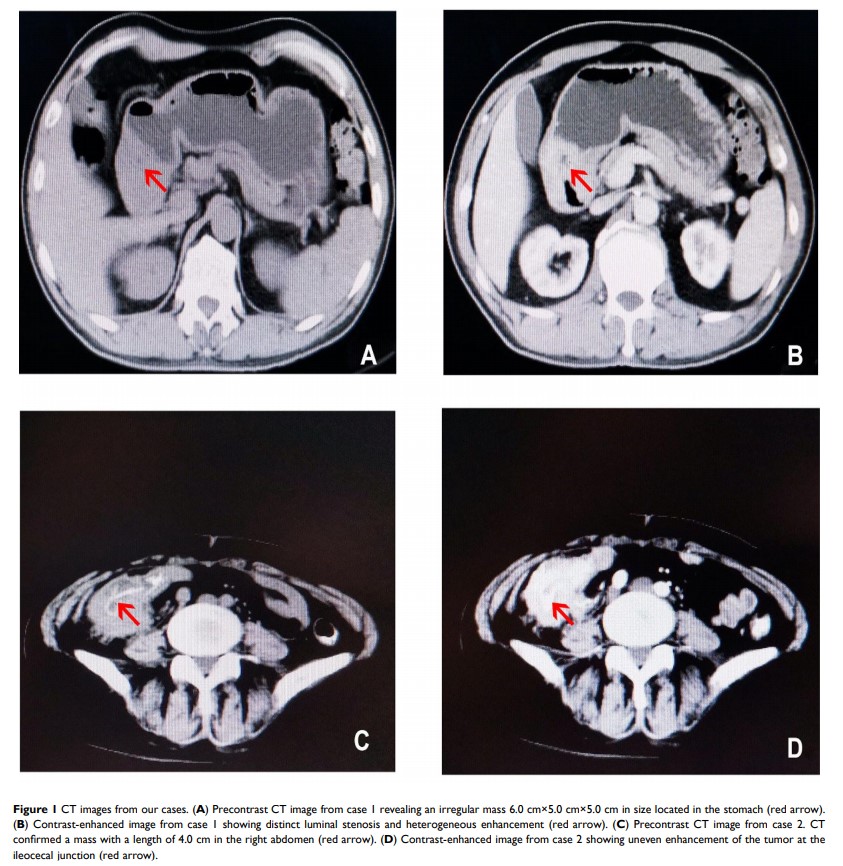

恶性胃肠道神经外胚层肿瘤:96 例患者临床病理及预后因素分析